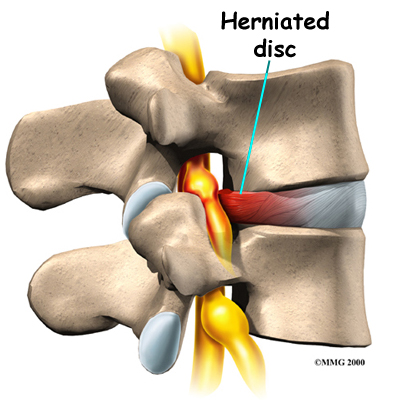

Herniation occurs when the nucleus in the center of the disc pushes out of its normal space. The nucleus presses against the annulus, causing the disc to bulge outward. Sometimes the nucleus herniates completely through the annulus and squeezes out of the disc.

Herniation causes pain from a variety of sources. It can cause mechanical pain. This is pain that comes from the parts of the spine that move during activity, such as the discs and ligaments. Pain from inflammation occurs when the nucleus squeezes through the annulus. The nucleus normally does not come in contact with the body's blood supply. However, a tear in the annulus puts the nucleus at risk for contacting this blood supply. When the nucleus herniates into the torn annulus, the nucleus and blood supply meet, causing a reaction of the chemicals inside the nucleus. This produces inflammation and pain. A disc herniation may also put pressure against a spinal nerve. Pressure on an irritated or damaged nerve can produce pain that radiates along the nerve. This is called neurogenic pain.

When the disc herniates completely through the annulus, it generally causes immediate symptoms, with sharp pain that starts in one hip and shoots down part or all of the leg. Commonly, patients no longer feel their usual back pain, only leg pain. This is likely because painful tension on the annulus releases when the nucleus pushes completely through.

Disc herniations produce inflammation when the nucleus comes in contact with the body's blood supply (mentioned earlier). The inflammation can be a source of throbbing pain in the low back and may spread into one or both hips and buttocks.

A herniated disc can press against a spinal nerve, producing symptoms of nerve compression. Nerve pain follows . It can be felt on the side of the upper thigh, in the calf, or even in the foot and toes.

Pressure on the nerve can also cause sensations of where the nerve travels down the lower limbs. If this happens, a person's reflexes slow. The muscles controlled by the nerve weaken, and sensation in the skin where the nerve goes is impaired.